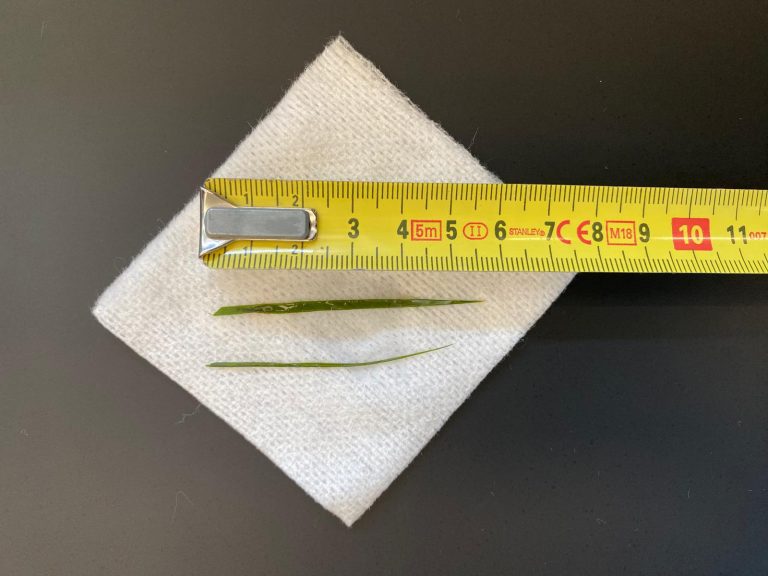

Bij navragen bij de eigenaar, bleek Joep 9 maanden eerder zijn rubberen speeltje kapot te hebben gebeten. Er was een stuk nog missende. Het bleek, na vergelijking van het materiaal, dat dit overeenkwam met de rubberen schijf die we uit de maag hadden gehaald. Dit betekent dat het speeltje 9 maanden in de maag aanwezig is geweest! De reden dat het nu problemen heeft gegeven is waarschijnlijk omdat hij bij de maaguitgang een beetje klem kwam te zitten.